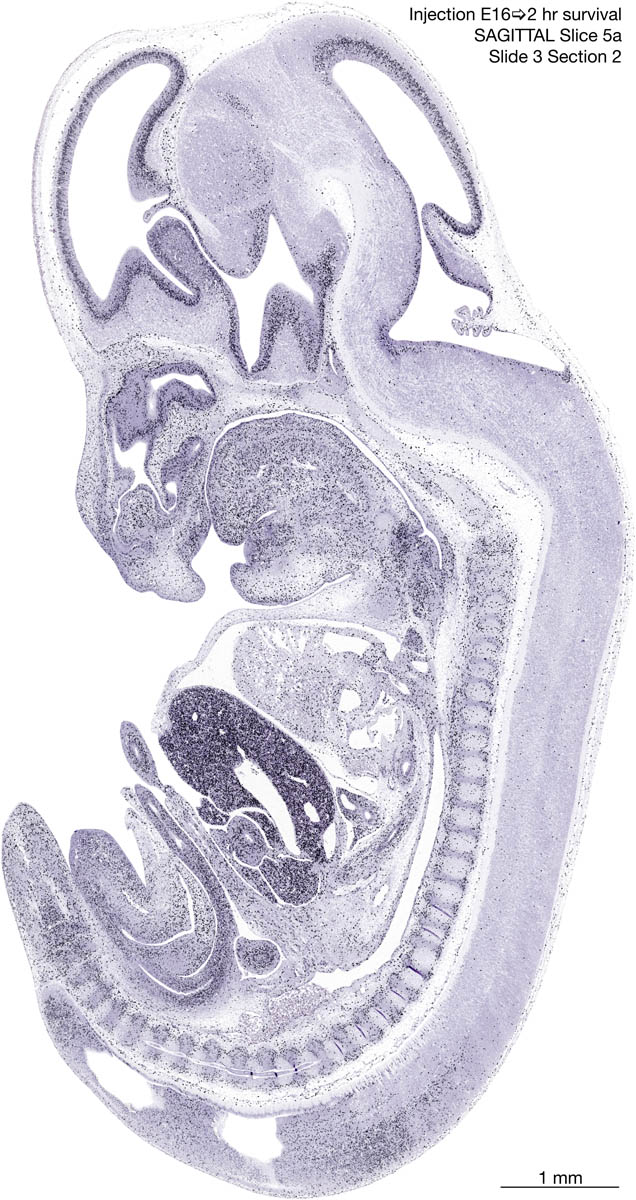

E16 2hr Survival Archived Images-Sagittal The following images are from a paraffin-embedded sagittally-sectioned E16 rat embryo exposed to tritiated thymidine 2 hours before death. Download: Large | High Res Download: Large | High Res Download: Large | High Res Download: Large | High Res Download: Large | High Res Download: Large | High Res Download: Large | High Res Download: Large | High Res Download: Large | High Res Download: Large | High Res Download: Large | High Res Download: Large | High Res Download: Large | High Res Download: Large | High Res Download: Large | High Res Download: Large | High Res Download: Large | High Res Download: Large | High Res Download: Large | High Res Download: Large | High Res Download: Large | High Res Download: Large | High Res Download: Large | High Res Download: Large | High Res Download: Large | High Res Download: Large | High Res Download: Large | High Res Download: Large | High Res Download: Large | High Res Download: Large | High Res Download: Large | High Res Download: Large | High Res Download: Large | High Res